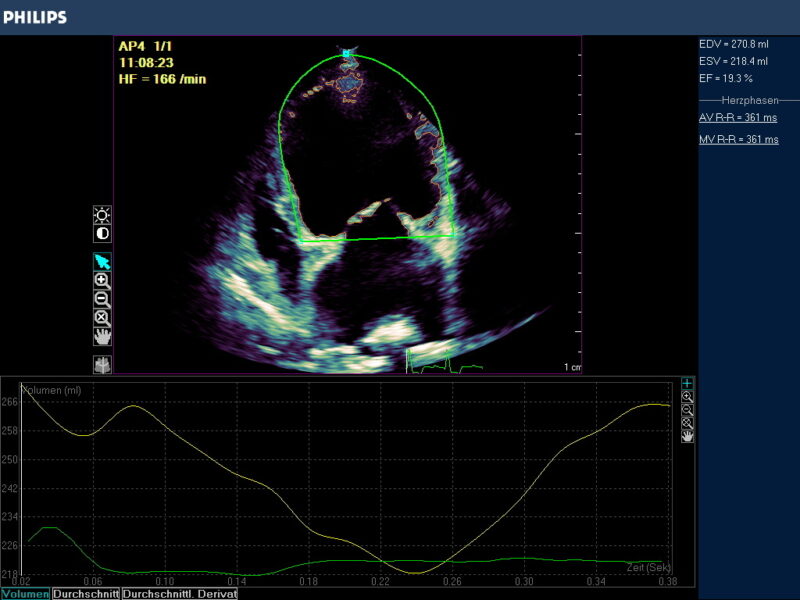

Das Ergebnis der GLS wird in negativ -%- Zahlen angegeben. In besonders schwer erkrankten Fällen kann die Zahl positiv werden! Je höher die negative Zahl angegeben wird desto stärker ist die Verformung bzw. Kinesie des Muskels. Darüber hinaus wird nach der Simpson Methode eine Ejektionsfraktion ermittelt , die in EF % angegeben wird (Abb. 3).

Globale Dysfunktion des linken Ventrikels durch Dilatation bei einer DKM oder infolge eines Ductus botalli persisitens oder einer chronischen Aorteninsuffizienz können bei hochgradigen Befunden sehr niedrige oder gar positive Strainzahlen hervorbringen. Die Ejektionsfraktion ist in diesen Fällen i.d.R. vermindert (Abb. 3).